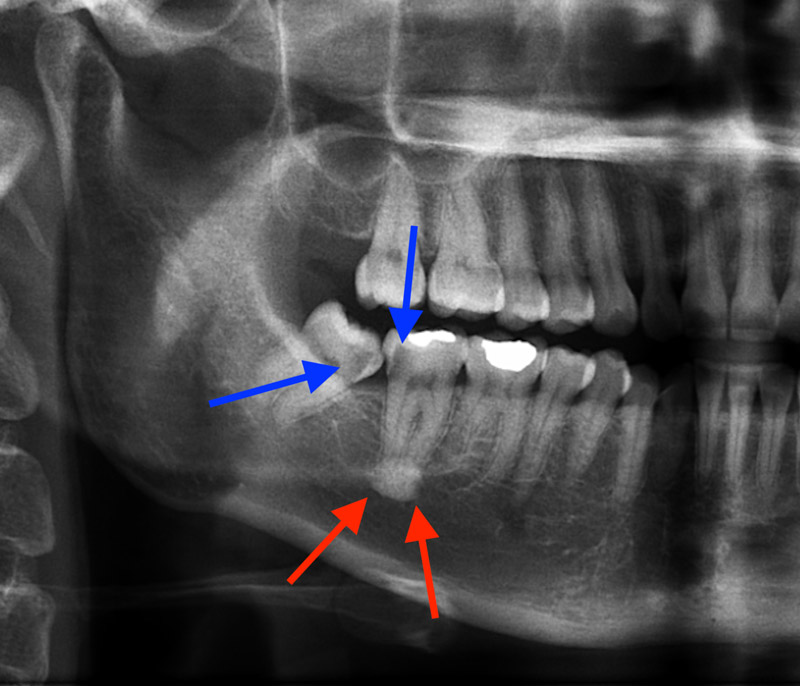

- Extraction of impacted or misplaced teeth

- Removal of retained tooth roots